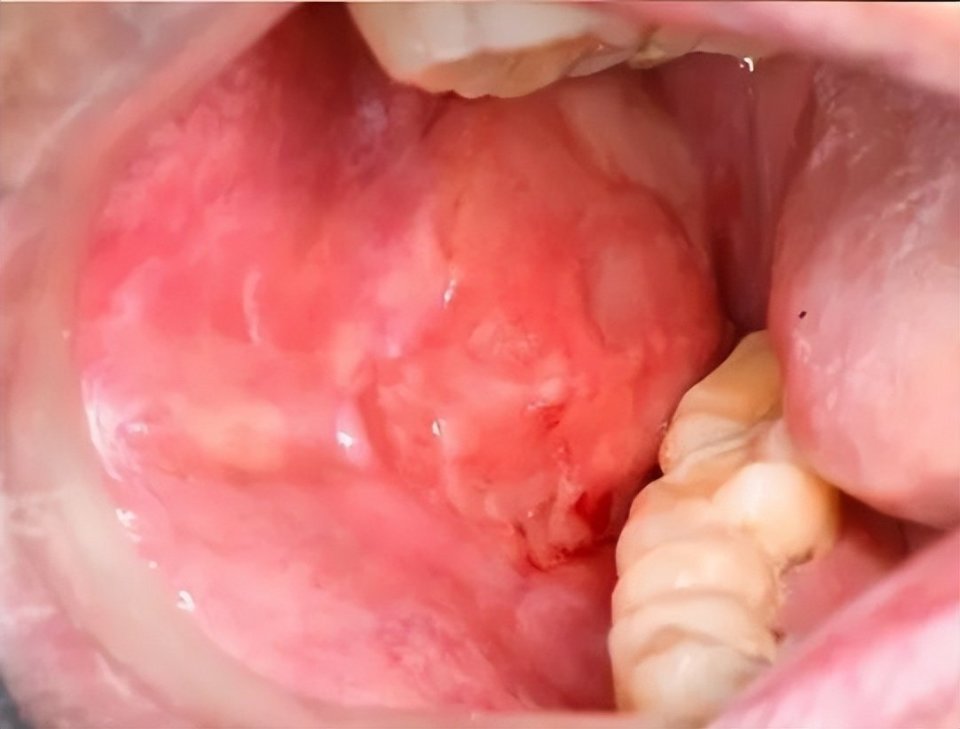

cGVHD口腔表现:红斑、苔藓样损害、溃疡及假膜形成(图片源自陶人川教授团队)